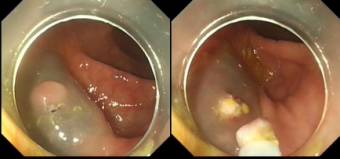

第一次内镜下取异物

一次在病房值班,来了一位老年患者,说自己食管癌术后、吻合口狭窄好多年了,平时能喝点稀的,中午可能吃菜没注意堵上了,非常难受,我立即联系胃镜室,准备好圈套器、五爪钳备用,进镜后发现食管吻合口严重狭窄,一黄豆样异物完全堵住了吻合口,给予五爪钳钳住,取出来一看,就是一粒黄豆,过程很顺利,老人家当时就说舒服多了,虽然后来取过多次鱼骨头,但这第一次取黄豆的经历还是印象深刻。

体会:一粒小小的黄豆,对常人来说可能没什么,但对某些患者来说,可能会带来痛苦。